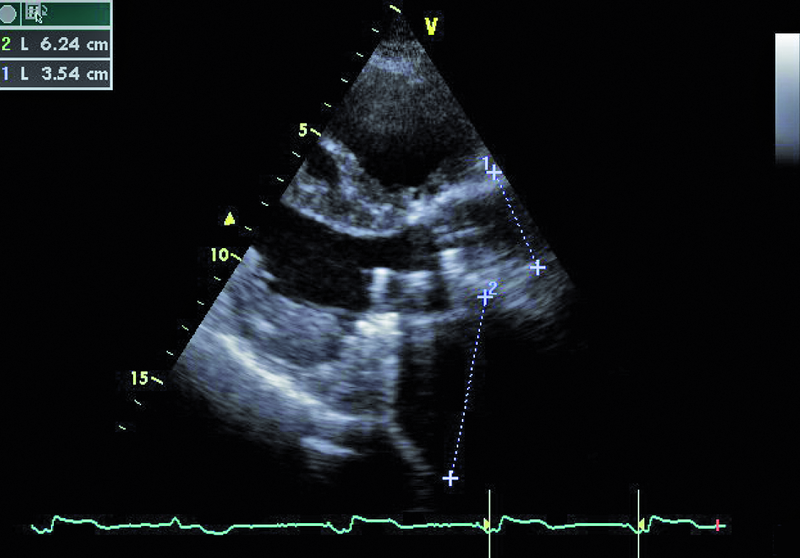

Mężczyzna, lat 59. Jakie patologie można rozpoznać na rycinach?

1. Powiększenie jamy lewego przedsionka (ryc. 1).